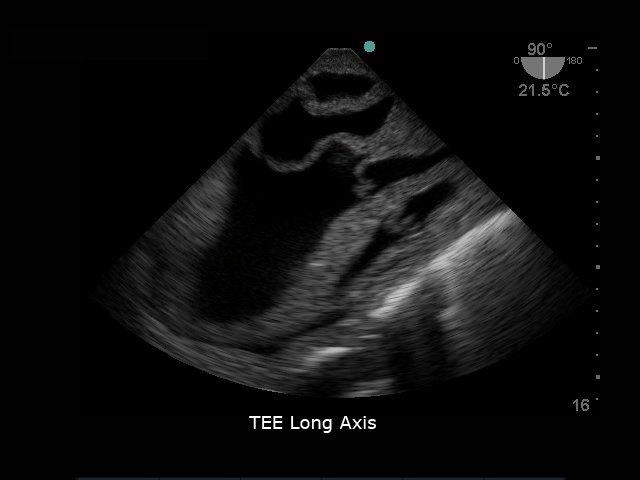

心脏超声训练模型

型号:PC-BP005/PC-BP005.01

模型具有逼真的心脏解剖超声图像,从不同角度可进行经食道和经胸廓心脏20个标准切面探查及测量,同时可进行超声引导下心包穿刺的完整流程训练。